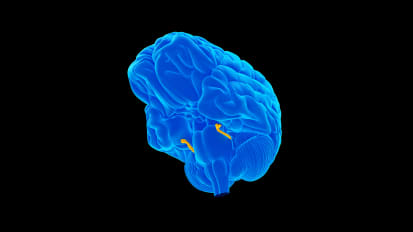

A New Application of Deep Brain Stimulation for Treatment-Resistant Schizophrenia

Johns Hopkins researchers report that after 24 weeks of deep brain stimulation to a particular part of the organ, a patient’s long-experienced hallucinations and suspicious delusions entirely ceased.